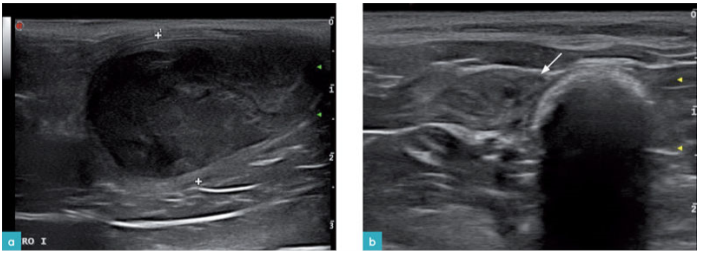

子宫内膜囊性增生和子宫蓄脓是激素介导性的,引发子宫内膜腺体囊性扩张,导致子宫腔内蓄积非炎性、无菌性以及粘性的液体,如有出现细菌污染,则会出现脓性及血性子宫内膜炎。子宫蓄脓通常继发于潜在的子宫内膜囊性增生,但并不是所有的子宫内膜囊性增生都会引起子宫蓄脓。虽然母猫子宫蓄脓较为常见,但却很少发生子宫内膜囊性增生。子宫蓄脓可发生在母猫交配但未受孕之后,1岁~10岁(平均7岁)均可发生。该病发病机理与犬相似,但通常病程会发展得更快(发情后1-4周),使用外源性孕激素也可引发此病。该病超声检查可见子宫扩张且充满液体。